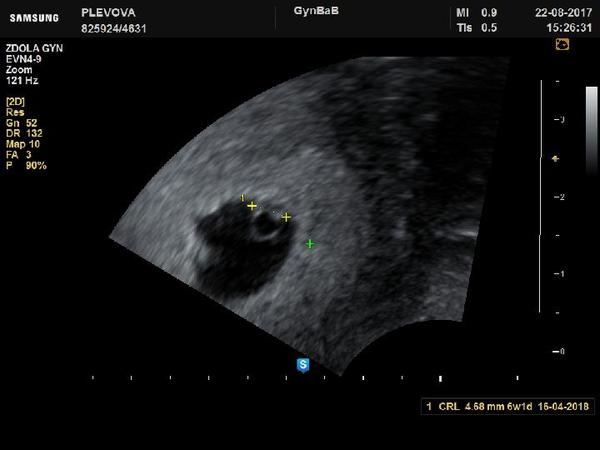

Těhotenský test. Dávám fotku. Co myslíte?

Tak nevim ... ☹ Dávám fotku, skuste posoudit...

@ka_rohli_na me prijde jak kdyby tam duch byl.

@ka_rohli_na myslim ze tohle neni duch ale slaba tehu carka...gratuluju potichounku😚